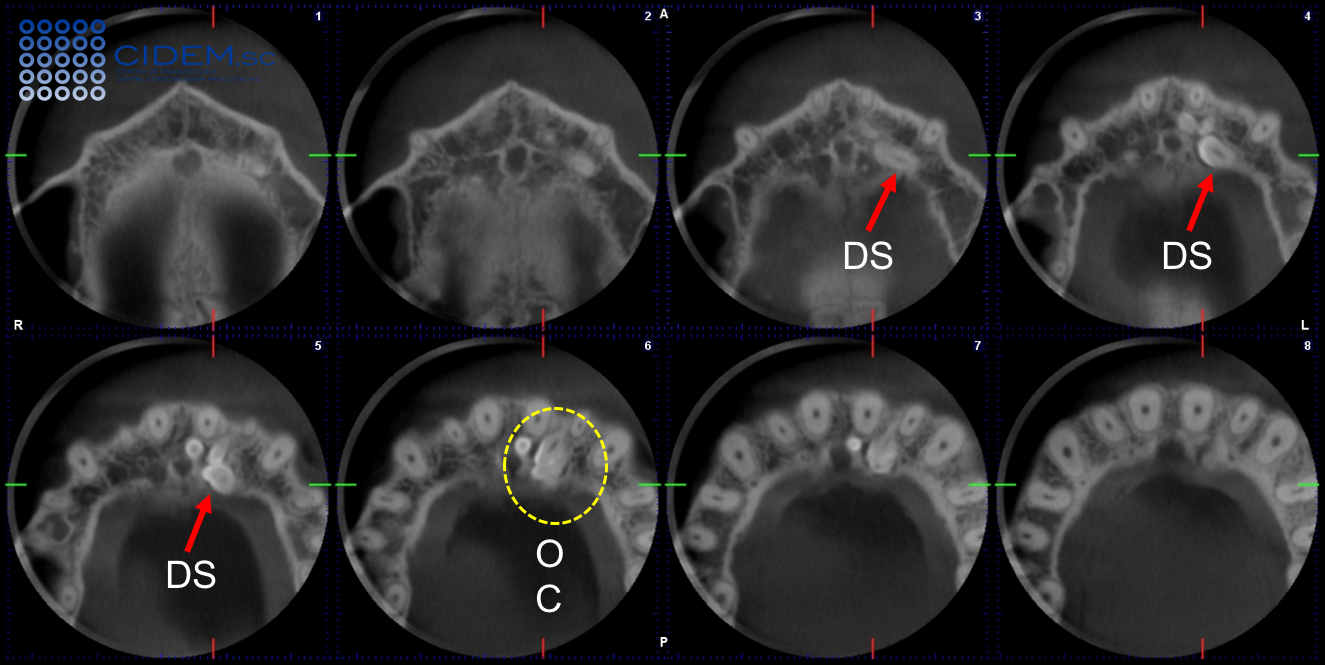

Figura 3. Vistas axiales de Tomografía Computarizada de Haz Cónico donde se indica (Flechas) la presencia de un diente supernumerario (DS), corona orientada hacia la línea media, palatal a la pared lateral del canal nasopalatino, tercio apical de la unidad dentaria 21  y  dentículos múltiples de un Odontoma Compuesto (OC-Círculo).

En el saco pericoronario del diente supernumerario, se evidencian imagénes hiperdensas múltiples, en forma de dentículos, rodeadas de halo hipodenso de bordes definidos y corticalizados, localizadas bucalmente al canal nasopalatino y al diente supernumerario previamente descrito, palatal al tercio apical de la pieza 21 (Figuras 3 y 4). Las reconstrucciones volumétricas en 3D confirmaron los hallazgos (Figura 5). Las imágenes presentan signos tomográficos de Odontoma Compuesto (OC).